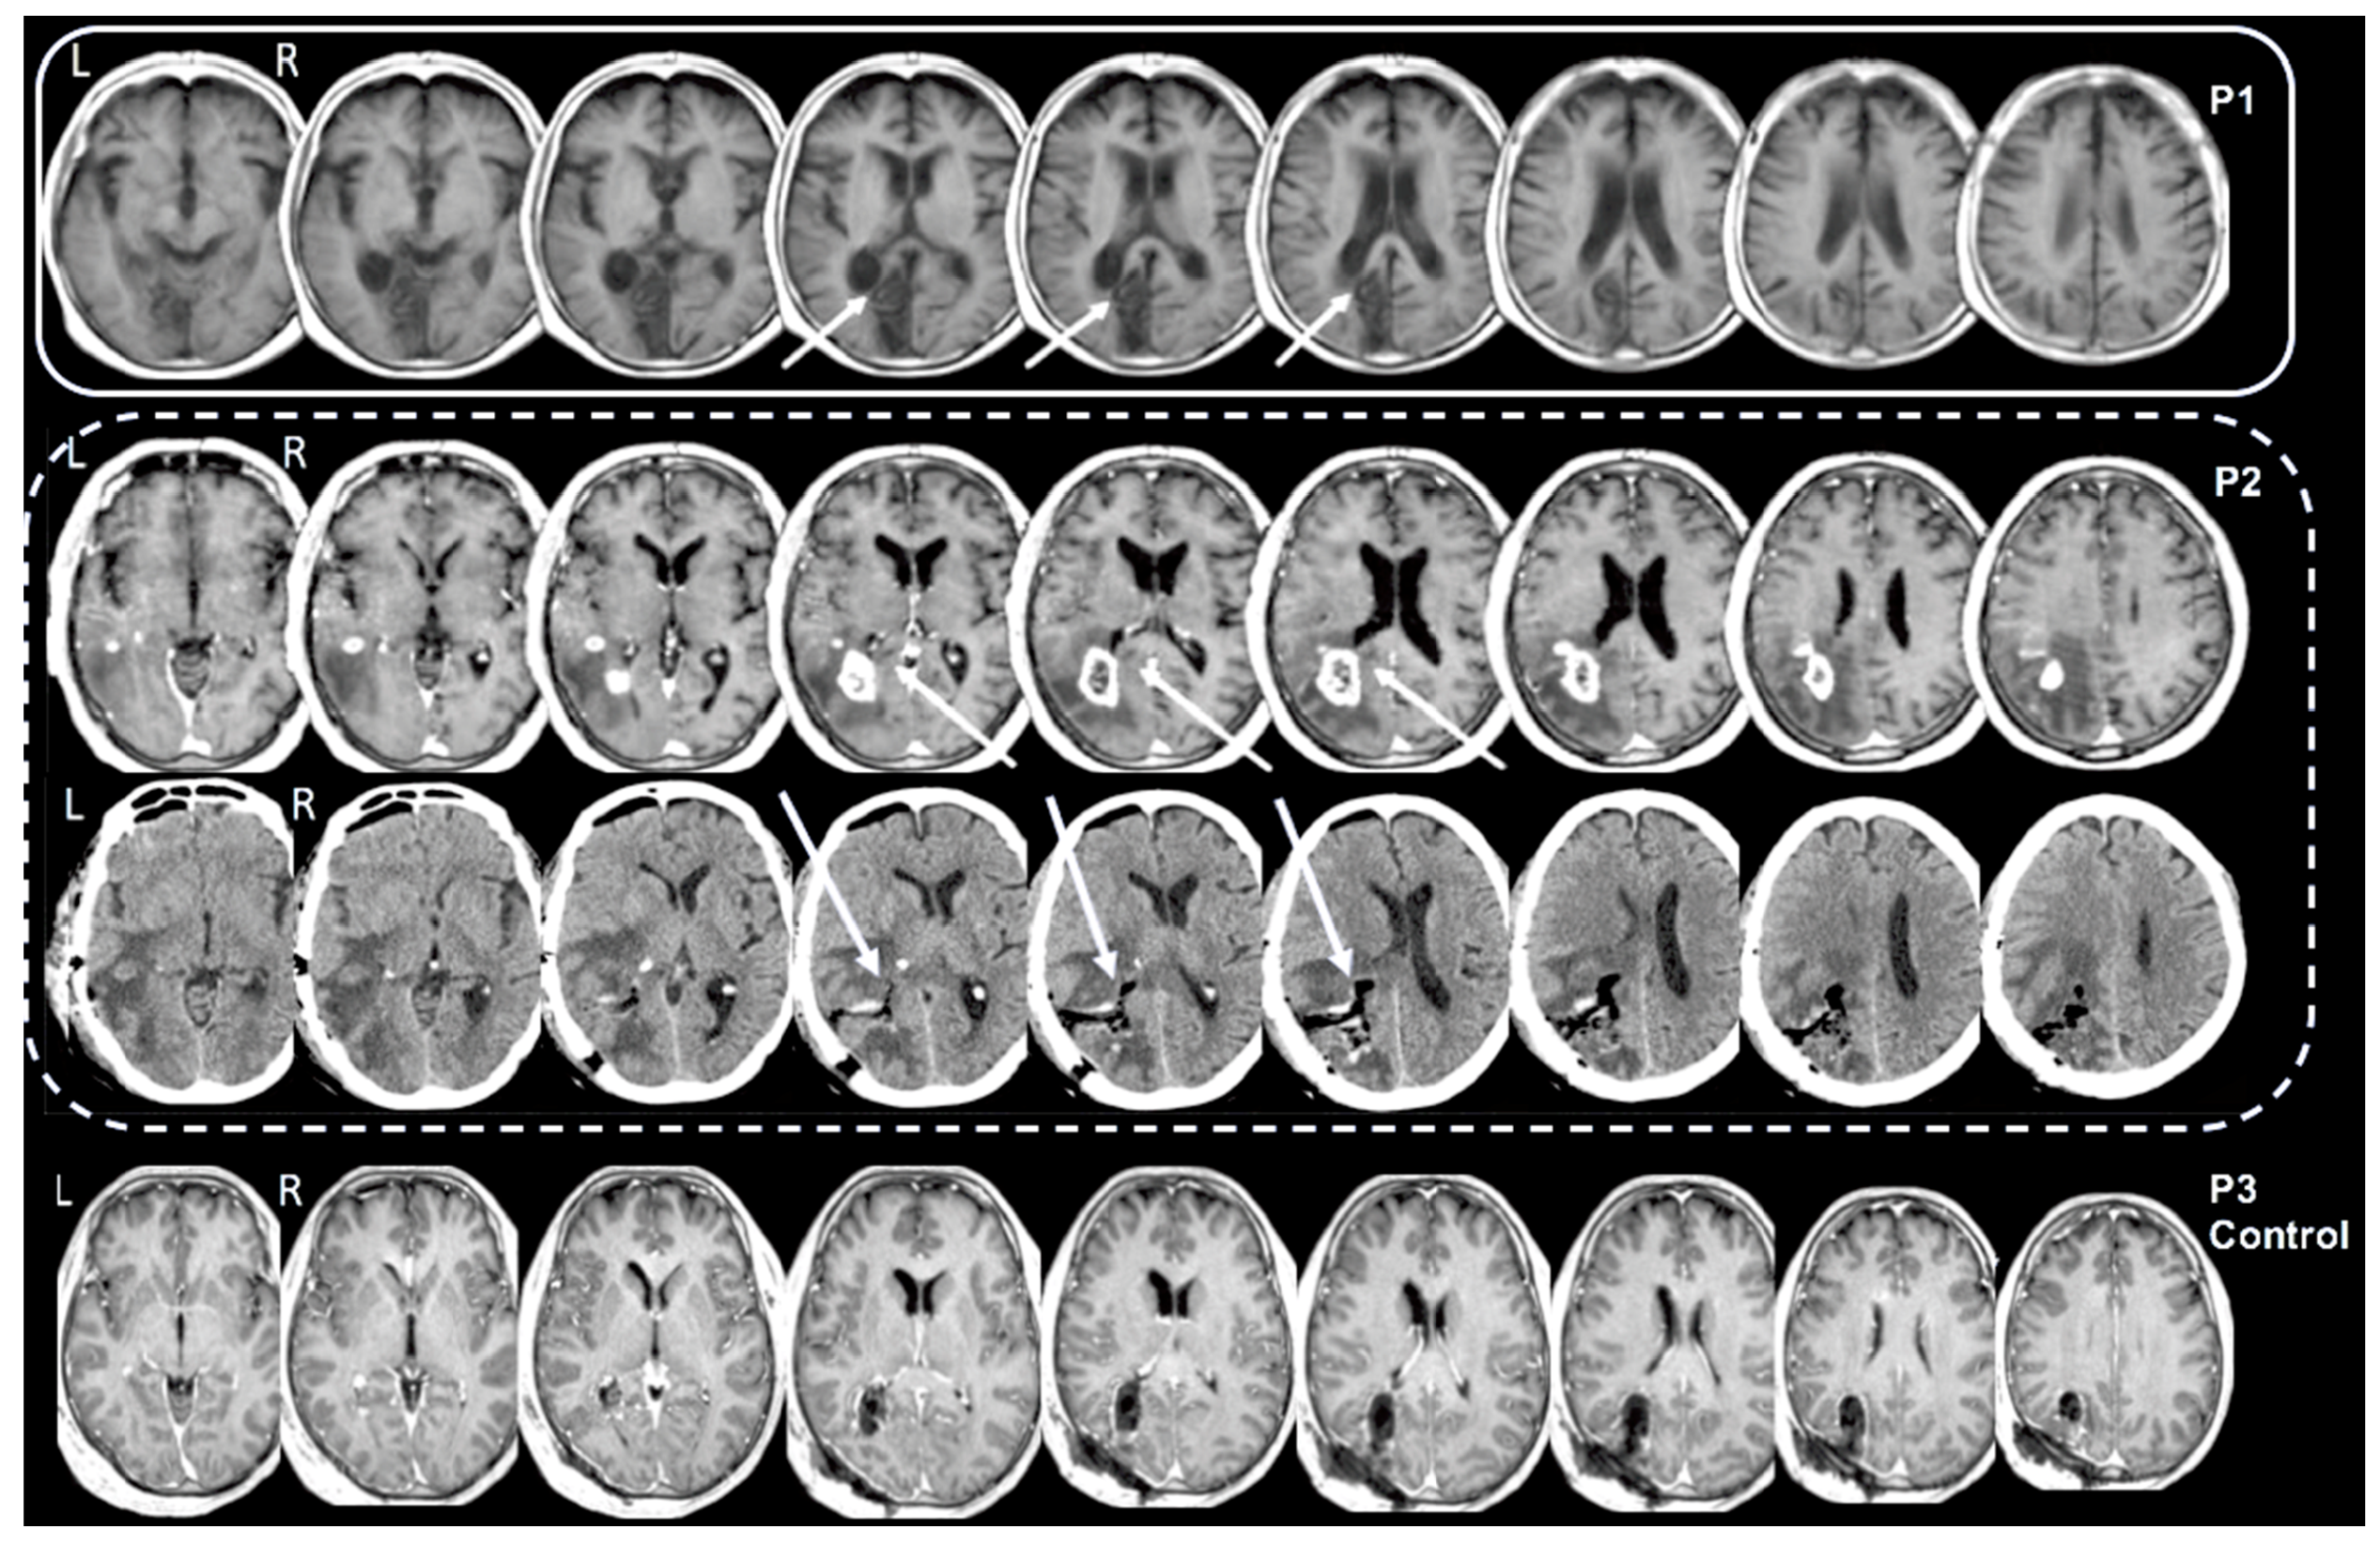

3.1. Localization of the Brain Lesions